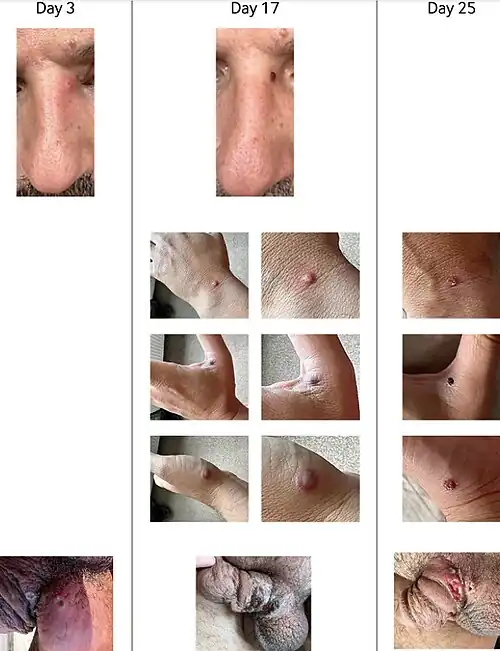

Mpox is a viral infection that manifests a week or two after exposure with fever and other non-specific symptoms, and then produces a rash with lesions that usually last for 2–4 weeks before drying up, crusting and falling off.[10] While mpox can cause large numbers of lesions, in this outbreak some patients experience only a single lesion in the mouth or on the genitals, making it more difficult to differentiate from other infections.[20] In previous outbreaks, 1–3 per cent of people with known infections had died (without treatment). In the 2022–2023 outbreak the rate of death was less than 0.2 percent. Cases in children and immunocompromised people are more likely to be severe.[21]

Mpox (/ˈɛmpɒks/, EM-poks; formerly known as monkeypox)[28] is an infectious viral disease that can occur in humans and other animals. Symptoms include a rash that forms blisters and then crusts over, as well as fever and swollen lymph nodes. The illness is usually mild, and most infected individuals recover within a few weeks without treatment. The time from exposure to the onset of symptoms ranges from three to seventeen days, and symptoms typically last from two to four weeks. However, cases may be severe, especially in children, pregnant women, or people with suppressed immune systems.[29][30][31]

In addition to more common symptoms, such as fever, headache, swollen lymph nodes, and rashes or lesions, some patients have also experienced proctitis, an inflammation of the rectum lining. CDC has also warned clinicians to not rule out mpox in patients with sexually transmitted infections since there have been reports of co-infections with syphilis, gonorrhea, chlamydia, and herpes.[98]